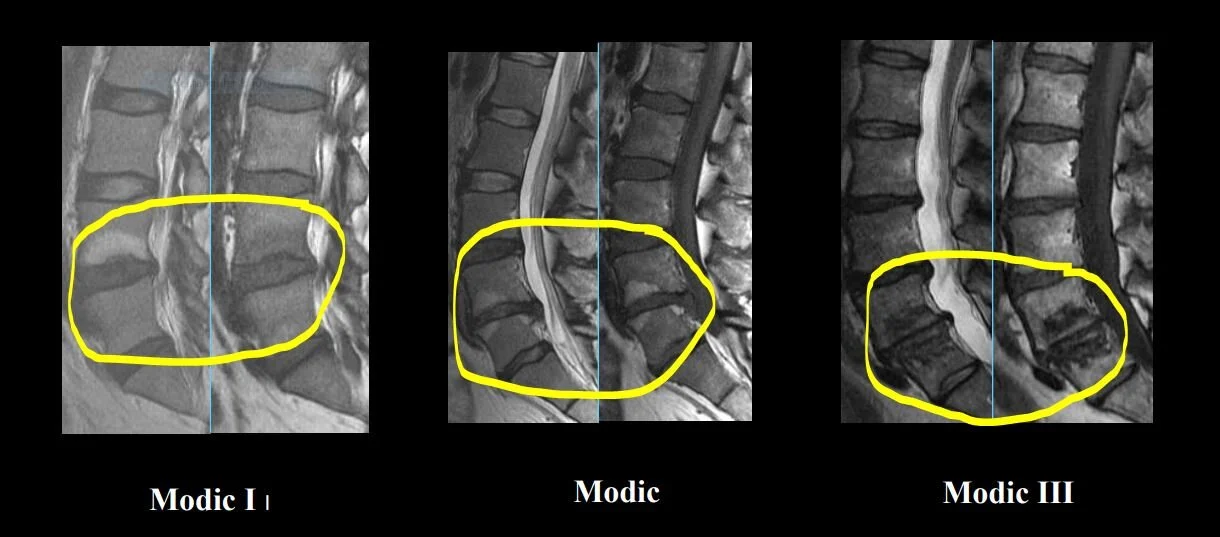

Modic Change and Chronic Pain

What are Modic changes? Modic changes are inflammatory disruptions in the vertebrae (bones) of our spine. This is part of a process that happens after a disc has been damaged for a long time (6+ months). Imagine the discs in the low back to be like the soft, white of an Oreo and the vertebra (bone) to be the hard, black cookie. What happens with Modic changes is the disc will infiltrate the bone. The Oreo is cracked and the soft, white center is pushing through the cookie. This creates swelling, inflammation, and even fracturing in the bone.